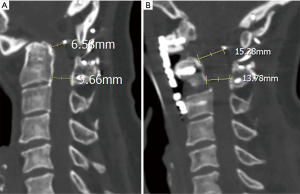

The postoperative anteroposterior open mouth and lateral radiographical images showed the plate and screws placed at good position (Figure 3A,B), the C2 body and odontoid process was ventrally slide and rotation at good position too, the spinal canal was increased significantly after operation (Figure 3C). The muscle strength grades of left upper limb, right upper limb, left lower limb, right lower limb was recovered to 4, 5, 4, 5 after operation, respectively.

Therefore, we design this anterior decompression through transoral “C2 slide and rotation” technique. Of this technique, the odontoid process is not resected, but slide and rotated ventrally, therefore, the spinal canal space is restored and direct decompression is achieved, the result of this technique is similar to the anterior controllable anti-displacement and fusion in lower level of cervical spine (22,23). In present case, the pre-operative sagittal distance between the upper-posterior portion of the odontoid process and transversal walking wire is 6.58 mm (Figure 4A), increase to the 15.28 mm after operation (Figure 4B). Moreover, the preserved odontoid process and C2 body served as an autogenous bone to reconstruct the anterior C1-C3 column, might have better biomechanical stability than the odontoid process resection technique.